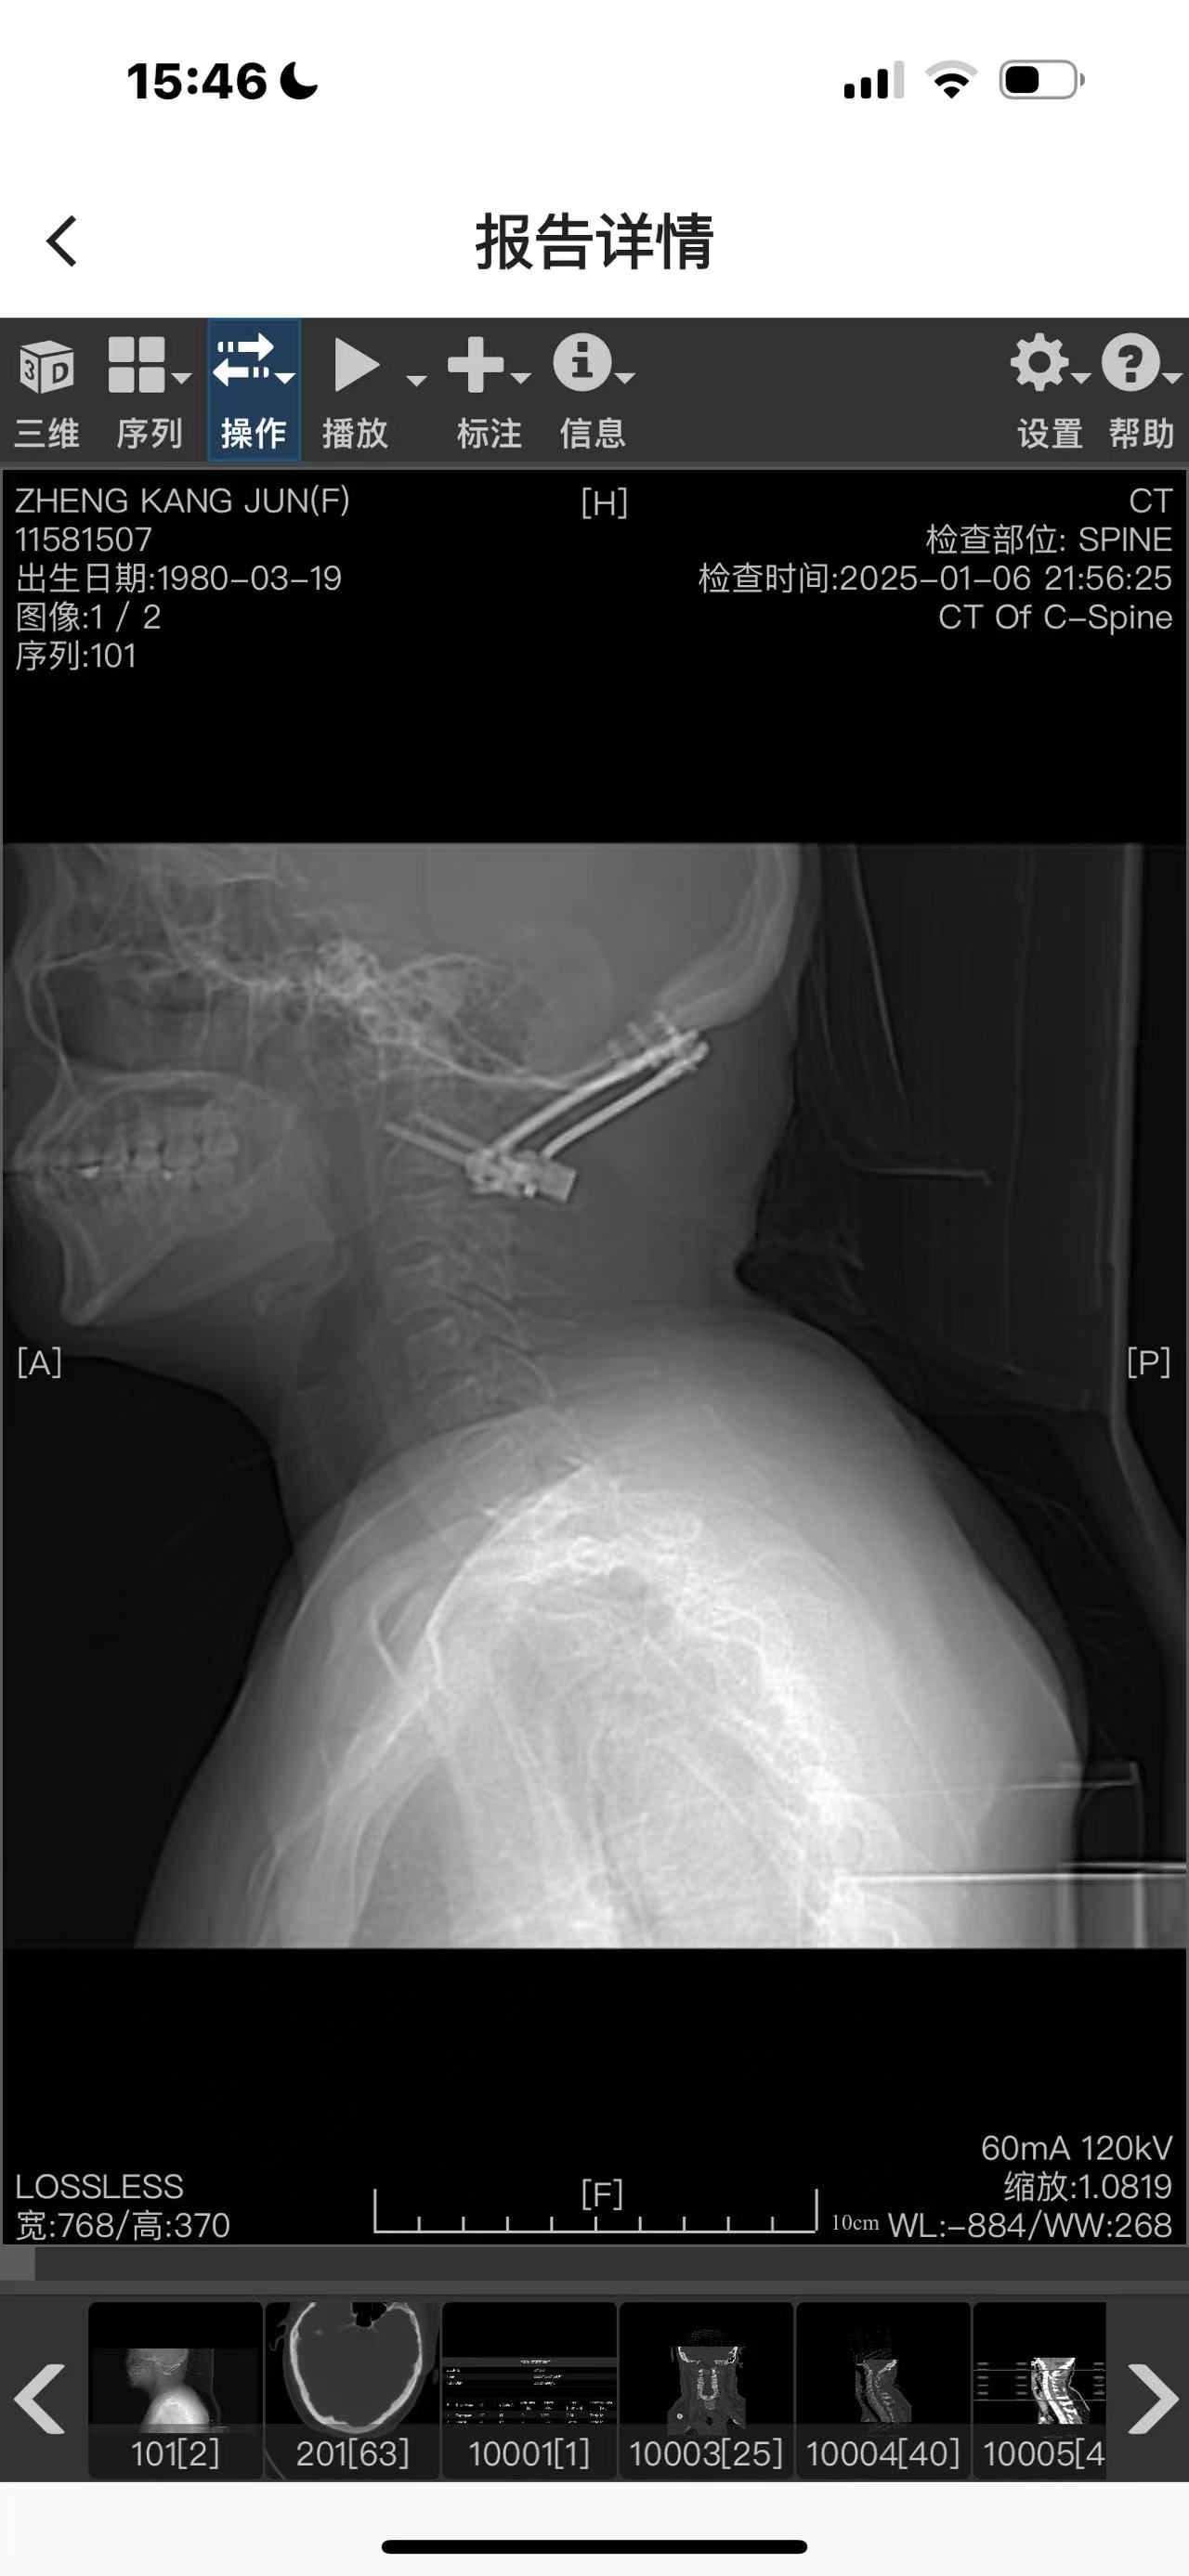

手术#

• 日期:2024.06

• 医院:上海长征医院

• 术后状况:没有复位

• 术后影像:

二次手术#

• 日期:2024.12.30

• 医院:人民医院

• 主刀:王超